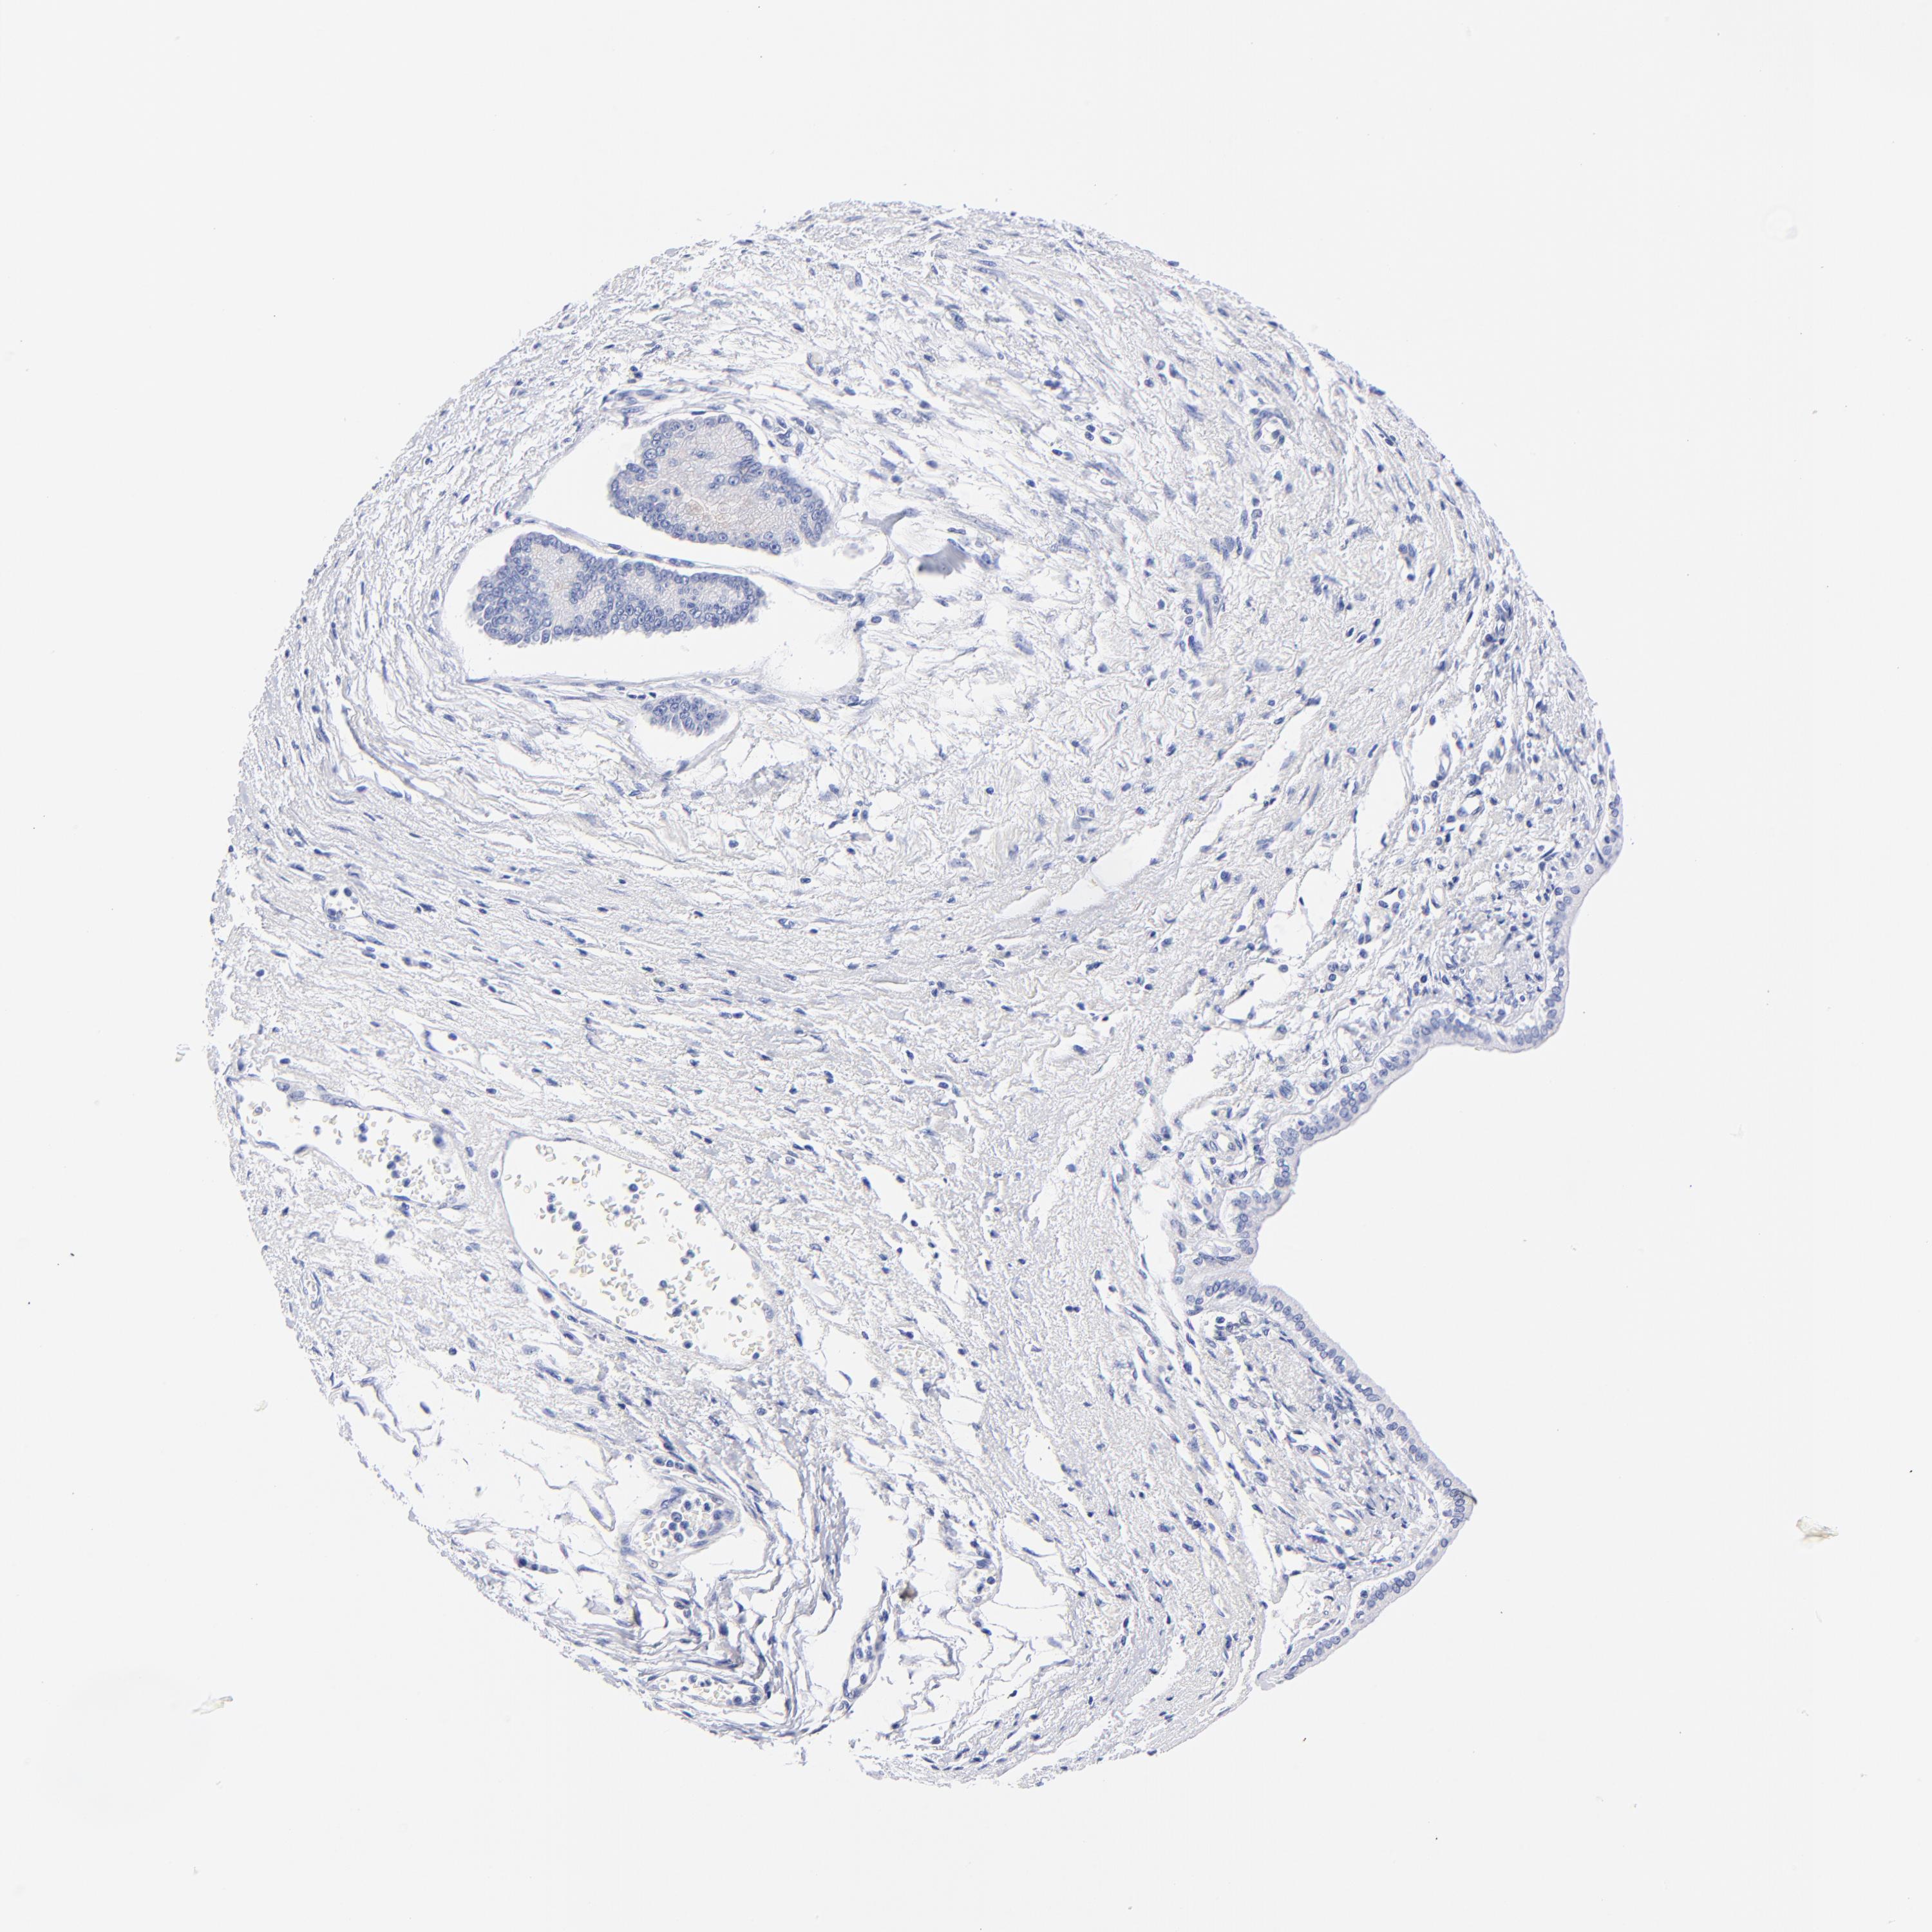

LIVER CANCER - Protein expressioni

A mouse-over function shows sample information and annotation data. Click on an image to view it in a full screen mode. Samples can be filtered based on level of antibody staining by selecting one or several of the following categories: high, medium, low and not detected. The assay and annotation is described here.

Note that samples used for immunohistochemistry by the Human Protein Atlas do not correspond to samples in the TCGA dataset.

Antibody stainingi

Antibody staining in the annotated cell types in the current human tissue is reported as not detected, low, medium, or high, based on conventional immunohistochemistry profiling in selected tissues. This score is based on the combination of the staining intensity and fraction of stained cells.

Each image is clickable and will lead to virtual microscopy that enables deeper exploration of all samples and also displays staining intensity scores, fraction scores and subcellular localization as well as patient and tissue information for each sample.

Antibody HPA003074

Staining

High

Medium

Low

Not detected

Intensity

Strong

Moderate

Weak

Negative

Quantity

>75%

75%-25%

<25%

None

Location

Nuclear

Cytoplasmic/membranous

Cytoplasmic/membranous,nuclear

Carcinoma, Hepatocellular, NOS

Cholangiocarcinoma